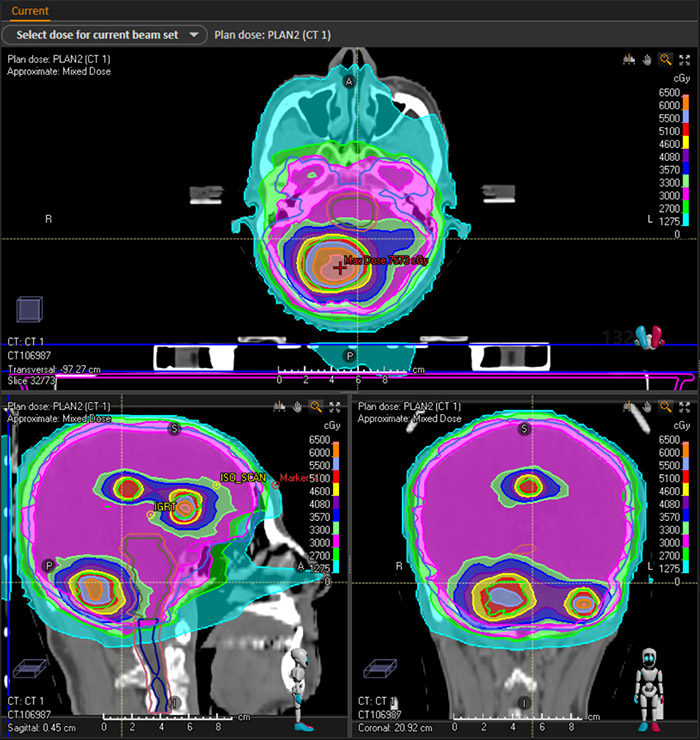

以下是一例肺癌多发脑转移病例的伽玛刀+直线加速器双头计划。通过DVH图以及剂量分布可以发现,比传统的直线加速器治疗,患者靶区的剂量得以提高,危机器官受量相对减少,达到了更佳的临床治疗效果。

剂量分布图

伽玛刀剂量分布图

直线加速器剂量分布图